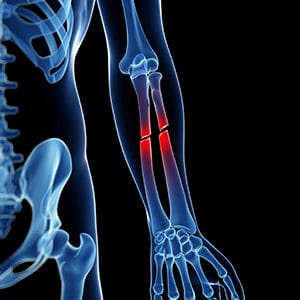

• Orthopaedic reconstruction: Once the patient is stable, orthopaedic injuries are addressed. This can include external or internal fixation of fractures, joint realignment, soft-tissue reconstruction and staged surgeries for open or contaminated wounds. Early fixation where appropriate helps reduce complications and facilitates rehabilitation.

Pelvic fractures with associated organ injury, multiple long-bone fractures, open fractures with severe soft-tissue loss, and distal tibial (Pilon) fractures are typical examples.